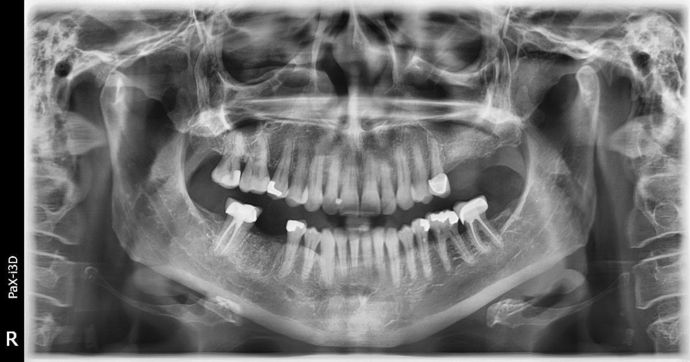

Dental Implants: Case 3 - Freeport

2 implants were placed on the upper left side, we had very little bone to work with. A 6 mm sinus augmentation was needed on the back implant and a 4 mm augmentation was needed on the more forward one. We did all of that at the time of implant placement here at the office. We finished the case using a fixed bridge to more evenly spread the load, we have a ton of bone that can be seen around the implants and it is still calcifying/healing towards the tops of the implants! I love complicated surgical cases like this, there is such a sense of accomplishment! I'll just borrow a saying here: WINNING!